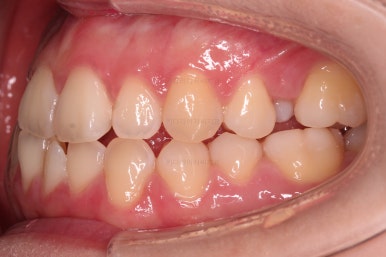

초진 시, 입안의 모습입니다.

아래 중앙선이 윗니의 정중선에 비해 우측으로 많이 쏠려있고요.

전반적으로 아래 치열이 우측으로 가 있어서 특히 송곳니 부분에서의 반대교합이 두드러졌어요.

(아래 송곳니가 위 송곳니보다 밖에 나와있는 상태)

가지런한 느낌, 교합, 중앙선, 반대교합 등 모든 면에서 개선이 되었고요.

얼굴 모습에서는 아랫니가 뒤로 들어감에 따라 웃는 모습도 윗니 위주로 보이면서 웃는 모습도 매우 좋아졌네요.

비대칭 부분은 뼈의 위치는 바뀌진 않았지만 교합을 바로 해줌으로 인해서 개선된 효과를 주고 턱관절 등 기능적으로도 개선이 되게 됩니다.